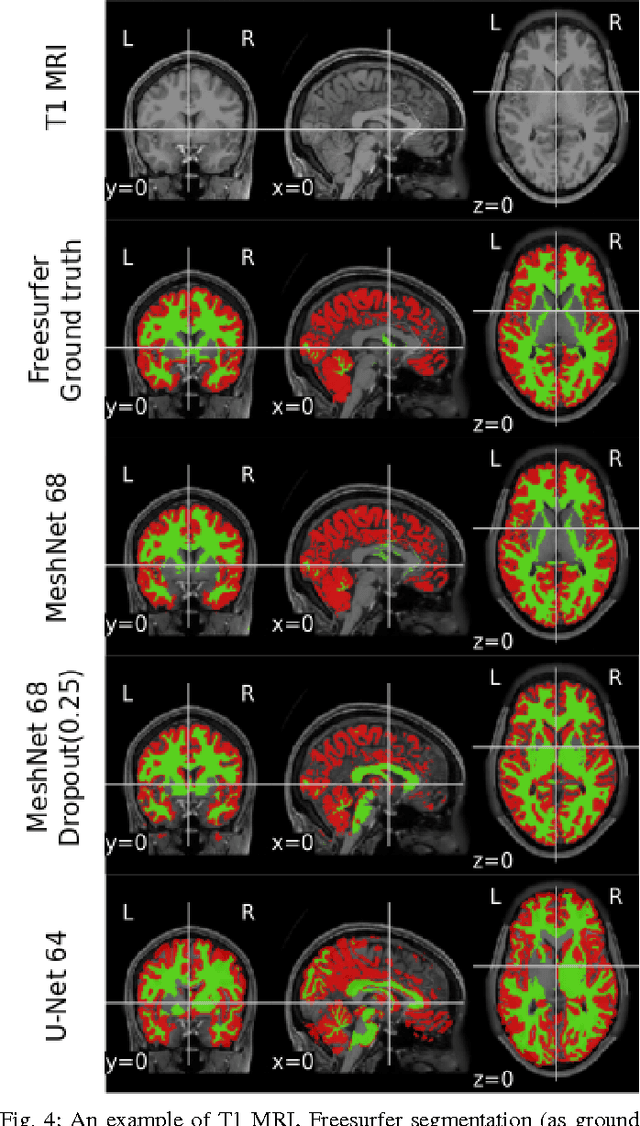

Abstract:Segmenting a structural magnetic resonance imaging (MRI) scan is an important pre-processing step for analytic procedures and subsequent inferences about longitudinal tissue changes. Manual segmentation defines the current gold standard in quality but is prohibitively expensive. Automatic approaches are computationally intensive, incredibly slow at scale, and error prone due to usually involving many potentially faulty intermediate steps. In order to streamline the segmentation, we introduce a deep learning model that is based on volumetric dilated convolutions, subsequently reducing both processing time and errors. Compared to its competitors, the model has a reduced set of parameters and thus is easier to train and much faster to execute. The contrast in performance between the dilated network and its competitors becomes obvious when both are tested on a large dataset of unprocessed human brain volumes. The dilated network consistently outperforms not only another state-of-the-art deep learning approach, the up convolutional network, but also the ground truth on which it was trained. Not only can the incredible speed of our model make large scale analyses much easier but we also believe it has great potential in a clinical setting where, with little to no substantial delay, a patient and provider can go over test results.